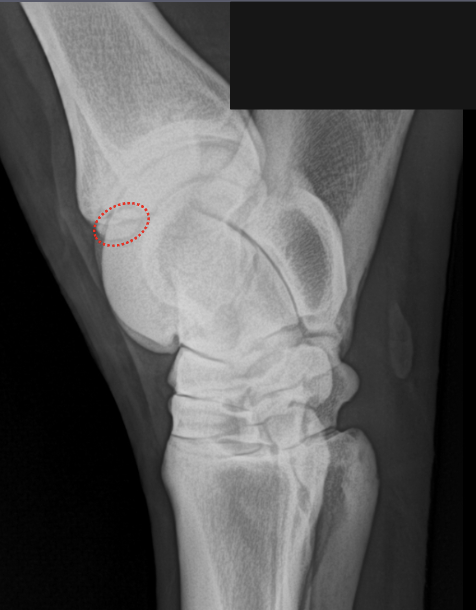

What is shown in these images?

A

Left: osteochondrosis of lateral trochlear ridge of talus

-“missing” bone that is cartilaginous instead of mineralized

Right: osteochondrosis of lateral trochlear ridge of talus

-lesion is the divot seen on lateral trochlear ridge

-red arrow is pointing to normal variation of the medial trochlear ridge